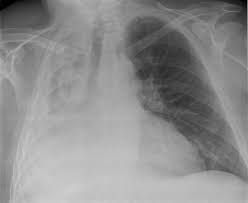

A massive hemothorax is defined as blood drainage >1,500 mL after closed thoracostomy and continuous bleeding at 200 mL/hr for at least four hours. Five patients were identified all requiring emergency surgery. Delayed massive hemothorax presented 63.6±21.3 hours after blunt chest trauma.